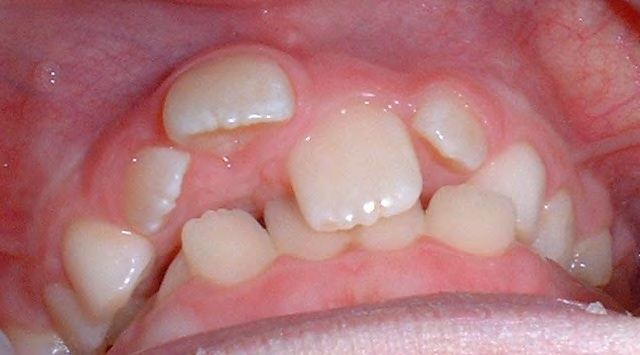

All of the patients below had been told they required extractions by orthodontists, some insisting that they could not be treated without extractions.

They were all treated without extractions, head gear or facemasks at Vakresmil and represent just a small sample of cases treated between 2004–2014.

The patient below had severe crowding of both upper canines and the lower right 5. The upper 4’s and 2’s were actually in contact.